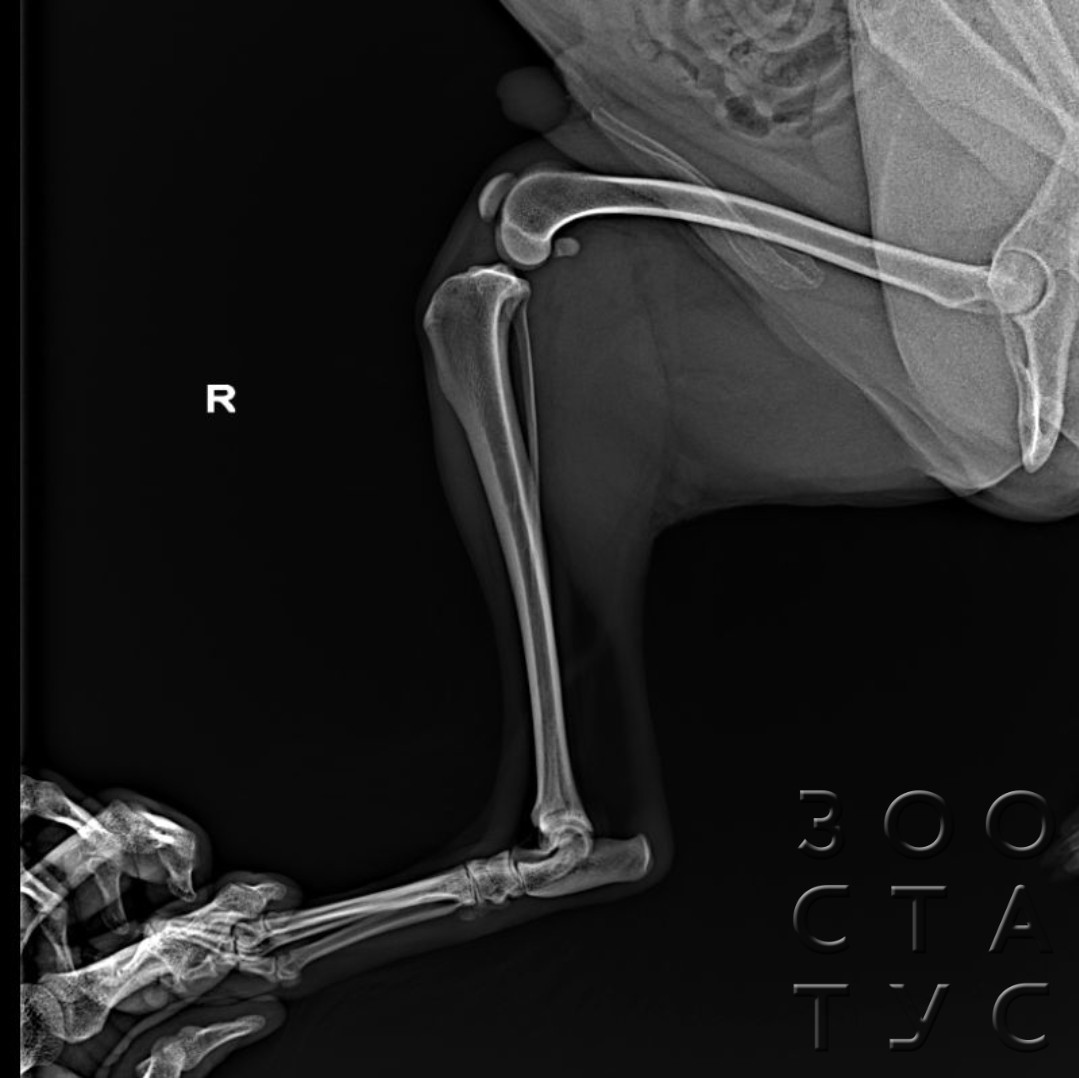

Рентгеновские снимки перелома лапы у кота: диагностика и лечение